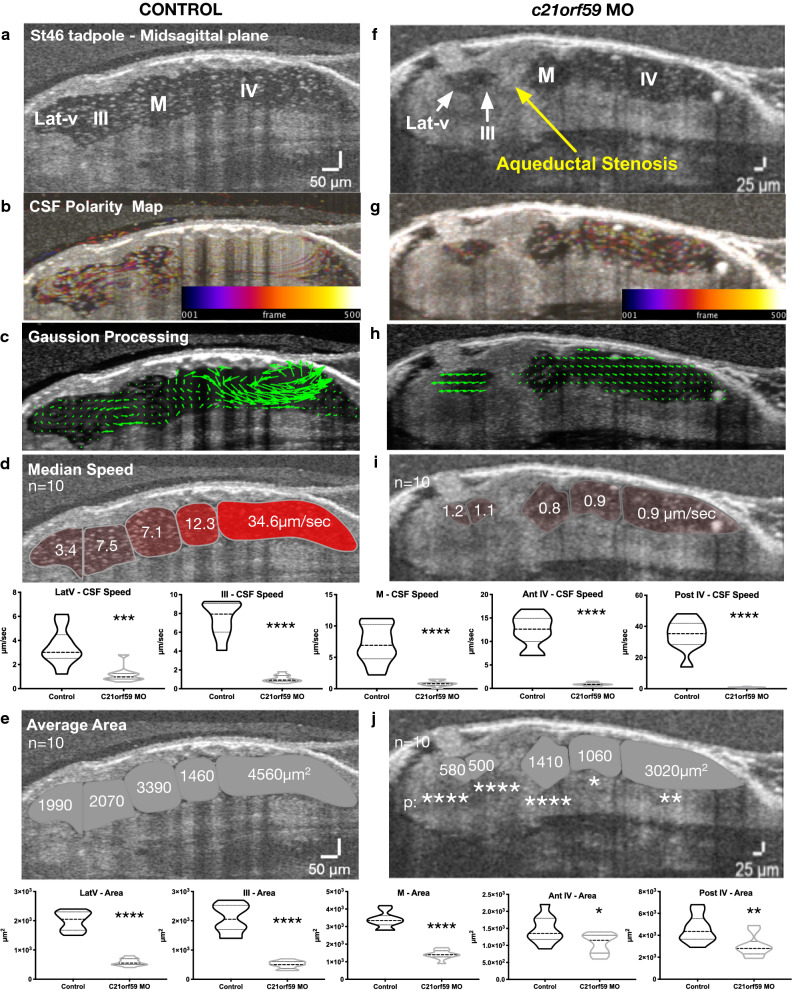

Fig. 7. Ependymal cilia driven flow is most impactful on rostral development. Mid-sagittal plane in vivo OCT imaging of stage 46 control and c21orf59 morphant tadpoles. a, f Midsagittal ventricular space, yellow arrow points the aqueductal stenosis. b, g CSF polarity flow map. c, h Post-Gaussian processing flow map. d, i Median compartmental flow speed. e, j Average compartmental area. *pâ<â0.01, **pâ<â0.001, ***pâ<â0.001, ****pâ<â0.0001